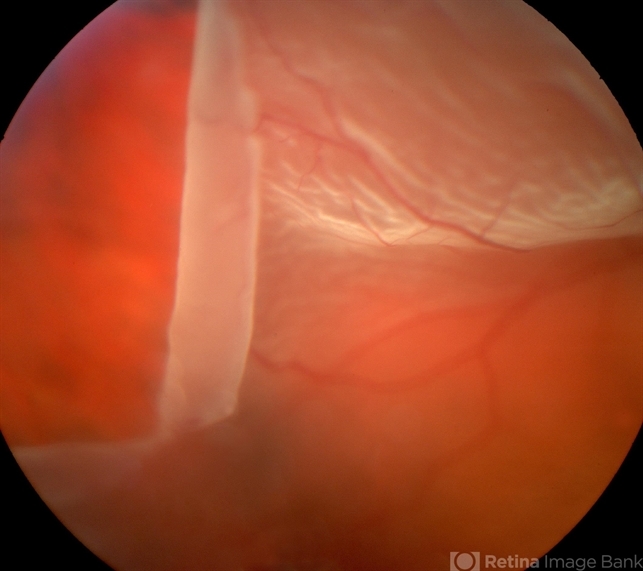

- retinal tear

- Giant retinal tear with radial element and rolled back posterior edge.